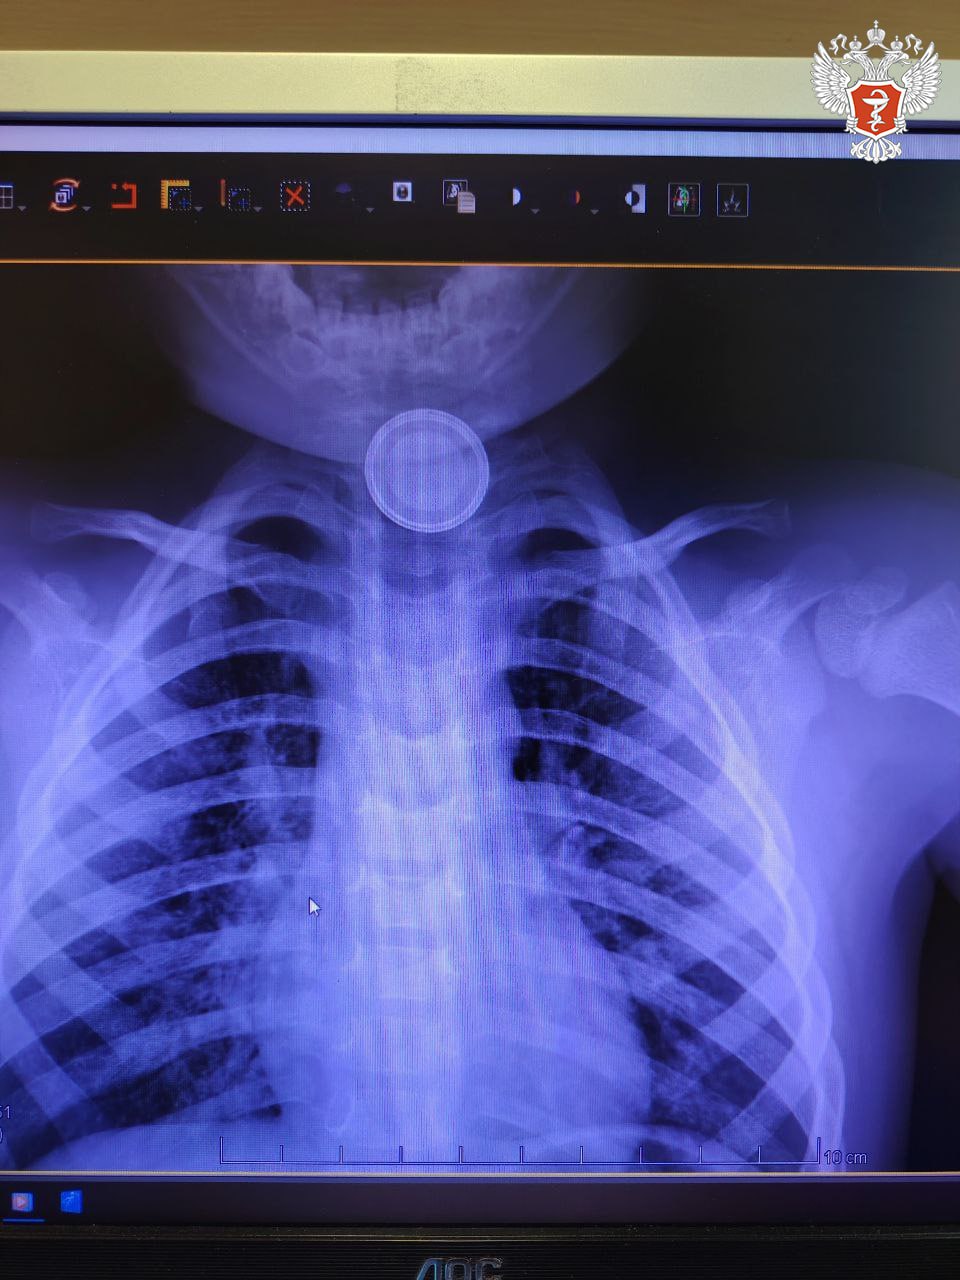

Годовалый ребенок поступил в Нижневартовскую окружную клиническую детскую больницу с затруднённым глотанием и слюнотечением. Врачи выполнили рентген и выявили круглое инородное тело в верхней трети пищевода.

Специалисты приняли решение о проведении экстренной операции и извлекли батарейку, но предмет успел нанести вред здоровью пациента.

— Батарейка повредила стенку пищевода, вызвав глубокий электрохимический ожог, занимающий половину просвета пищевода. Учитывая тяжесть состояния от полученной травмы, ребенок был госпитализирован в отделение реанимации, где проводилась интенсивная терапия. После стабилизации состояния малыша перевели в детское хирургическое отделение, где было продолжено ранее начатое консервативное лечение, — рассказал детский хирург Нижневартовской окружной клинической детской больницы Вячеслав Воронин.